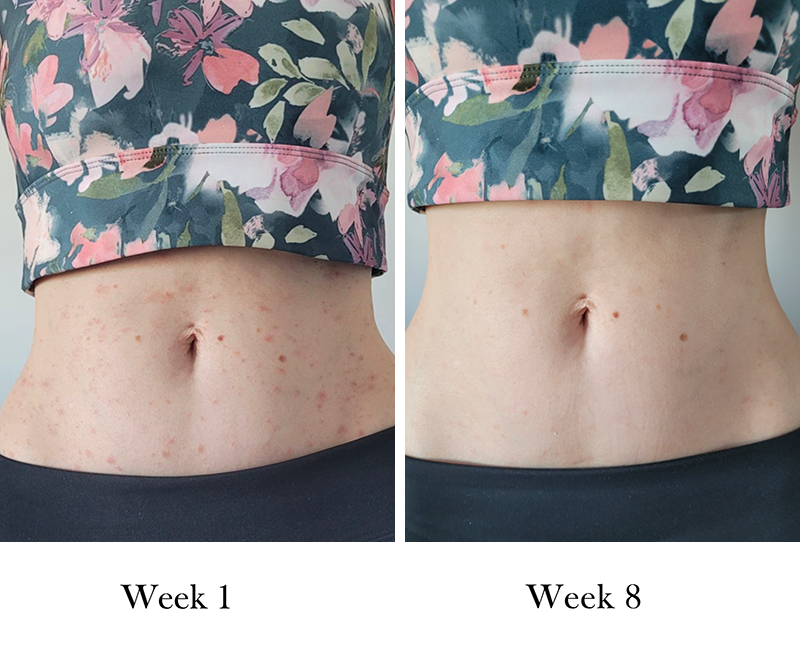

Seborrheic Dermatitis

"There has been a significant improvement in the dermatitis. It has largely cleared from my scalp and hairline."

Chris

Brilliance Unflavoured

"My skin condition has almost completely cleared up which is just amazing."

Lana

Enrich Collagen Body ButterShare your before and after journey with hashtag #kissedearth